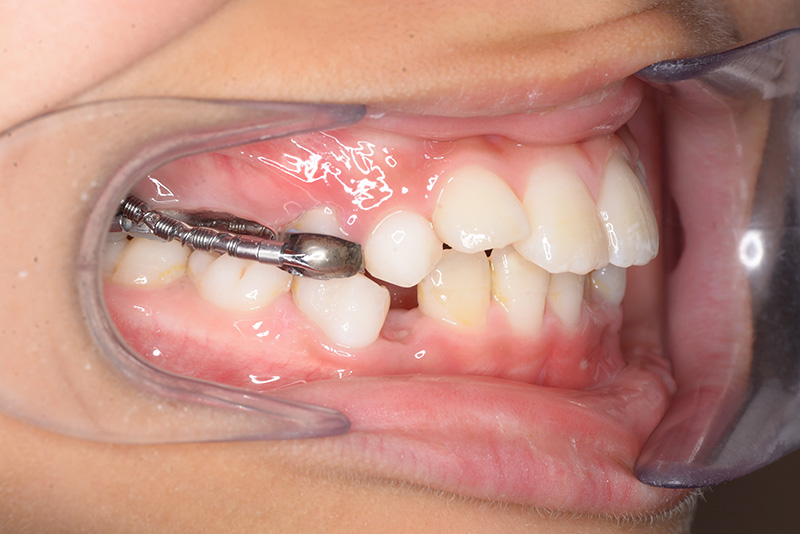

| 使用装置 | GMD、Nanceホールディングアーチ | ||||||

| 口腔内所見 | over jet 2.5mm、over bite 2.0mm、右側大臼歯関係はEnd on class Ⅱ、上顎左側Eは早期喪失により左側大臼歯関係はFull classⅡ、右側Eは6の異所萌出により歯根吸収が進行したため一般歯科医院にて抜去済みであった。 |

| パノラマ所見 | 上顎両側6、特に左側6は近心傾斜が認められ、両側5の萌出スペース不足が認められた。 |